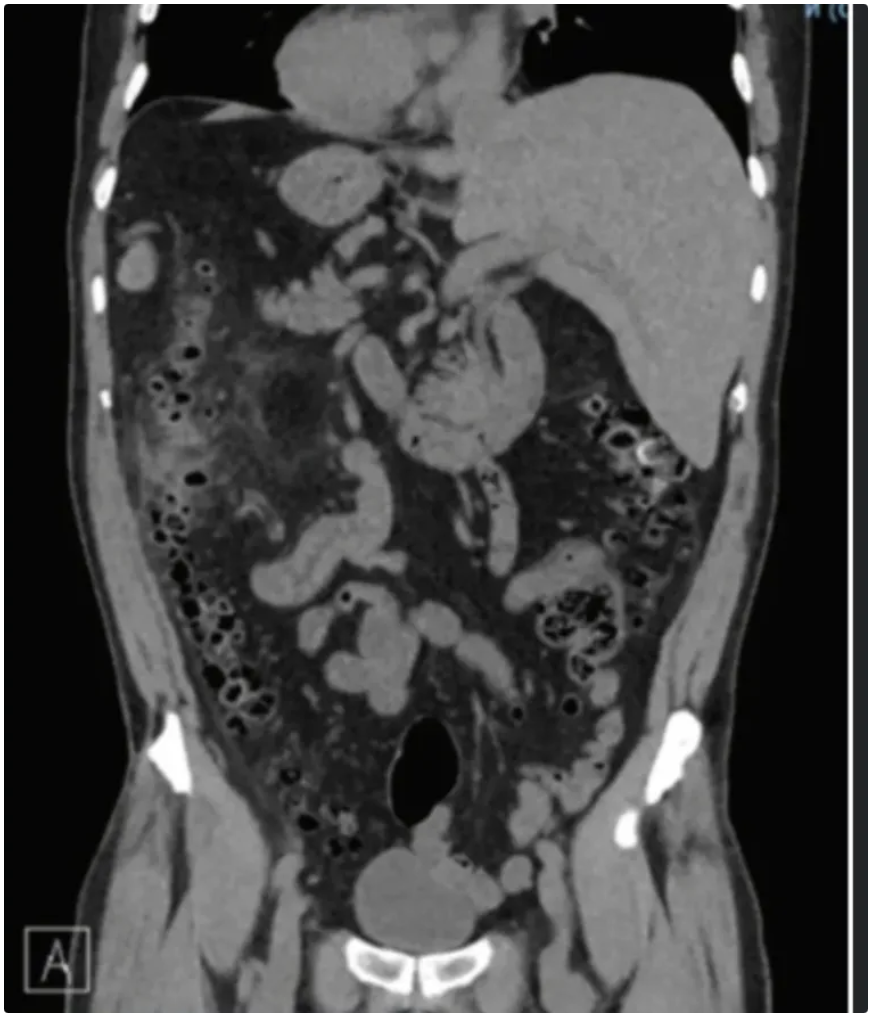

Achado?

A

DIVERTÍCULO COM AR DENTRO DELE EM CÓLON DE PAREDE ESPESSADA E BORRAMENTO DE GORDURA